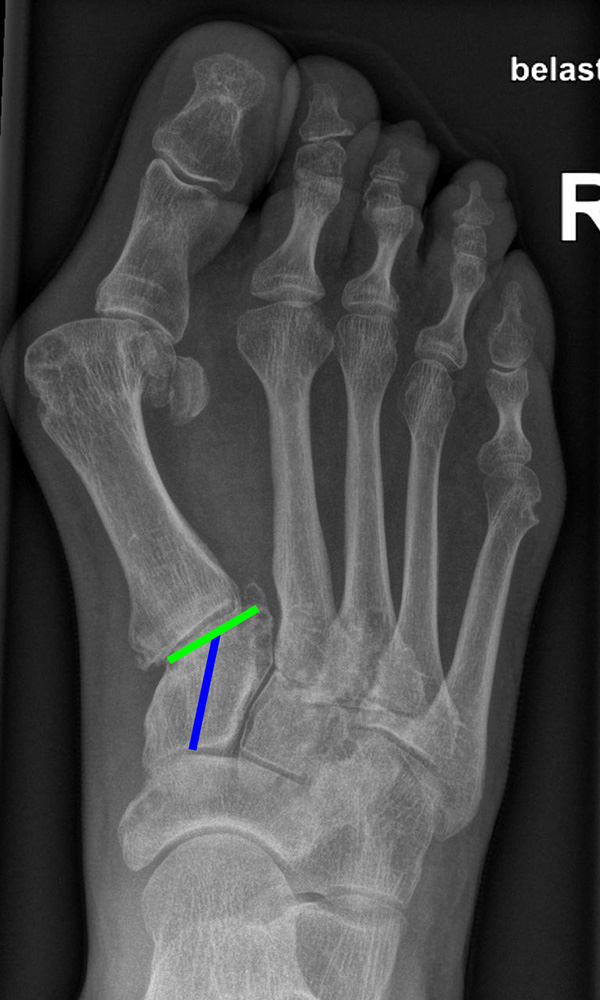

Gelenkflächenwinkel

DMAA (Distal metatarsal artikular angle, Syn. Gelenkflächenwinkel): Winkel zwischen der Achse des Os metatarsale I (rot) und dem Lot auf die distale Gelenkflächenebene (blau) des Os metatarsale I. Die Gelenkflächenebene (grün) wird definiert durch zwei Punkte, welche die mediale und laterale Begrenzung der Gelenkfläche definieren (Norm: <10° 5). Die Projektion des DMAA ist stark abhängig von der Rotation des Os metatarsale I 7. Daher ist bei der operativen Behandlung des Hallux valgus eine Beurteilung häufig erst nach Korrektur der Pronationsstellung des Os metatarsale I möglich. Tendenziell wird der DMAA auf präoperativen Röntgenaufnahmen überschätzt.

Beurteilung eines Metatarsus adductus

Medial wird eine Linie von der medialen Begrenzung des TMT1-Gelenks und der medialen Begrenzung des Talonavikulargelenks (TN) gezeichnet. Auf der lateralen Seite des Fußes wird eine zweite Linie von der lateralen Begrenzung des Calcaneocuboid-Gelenks (CC) zur lateralen Begrenzung des TMT5-Gelenks gezeichnet. Die Mittelpunkte beiden Linien werden verbunden (blau). Der Winkel zwischen der Achse des Os metatarsale II (rot) und dem Lot auf Verbindungslinie (grün) ist ein Maß für die Stellung des Vorfußes zur Fußwurzel. Dieser Wert dient zur Charakterisierung eines Pes adductus. Ein Pes adductus kann zu einem normwertigem Intermetatarsale I/II Winkel führen, obwohl klinisch eine ausgeprägte Hallux valgus Deformität vorliegt 8. (Norm: ±13° 9.

TMT-1-Gelenk dorsoplantar (Tarsometatarsale-1-Gelenk)

In der dorsoplantaren Aufnahme kann ein Versatz der Gelenkfläche im TMT-1 Gelenk auf eine Instabilität hindeuten. Phasenweise wurde auch die Ausrichtung der distalen Gelenkfläche des Os cuneiforme I (grün) zur Achse des Os cuneiforme I (blau) als Risikofaktor diskutiert, hat sich aber aufgrund der starken Projektionsabhängigkeit nicht bewährt 10. (Norm 0-15° 9).